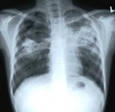

Каждый пятый больной туберкулезом вологжанин неизлечим

Каждый пятый вологжанин, заболевший туберкулезом, неизлечим. С 1987 года во всем мире, в том числе - в России, нет новых противотуберкулезных препаратов. Об этом, в частности, шла речь в Вологде сегодня, 7 апреля, на пресс-конференции, посвященной Всемирному Дню здоровья, сообщает ИА «СеверИнформ — Новости Вологодской области".

«Бактерии выделяют устойчивые и неустойчивые к препаратам, - рассказывает врач-фтизиатр областного противотуберкулезного диспансера Алла Воронина. Если человек заразился неустойчивыми к препаратам бактериями, то на эту туберкулезную палочку действуют все противотуберкулезные препараты. Но в последнее время растет количество больных, которые заражаются устойчивыми микобактериями туберкулеза. То есть которые не реагируют на те или иные противотуберкулезные препараты. Есть понятие о множественной лекарственной устойчивости. Это когда палочка устойчива к основным препаратам. И есть понятие о широкой лекарственной устойчивости. Когда палочка устойчива практически ко всем противотуберкулезным препаратам. У нас есть проблема, что иногда нам туберкулез просто-напросто нечем лечить. Например, в 2002 году впервые выявлена множественная лекарственная устойчивость у 11,6% больных. А в прошлом году множественная лекарственная устойчивость уже 20,4 % по области. То есть каждый пятый человек изначально заболевает устойчивыми формами туберкулеза».

Отметим, что эту лекарственную устойчивость может сформировать сам пациент, отказываясь принимать те препараты, которые прописал специалист, или прервав лечение. Медики советуют не заниматься самолечением и следовать всем предписаниям врача.